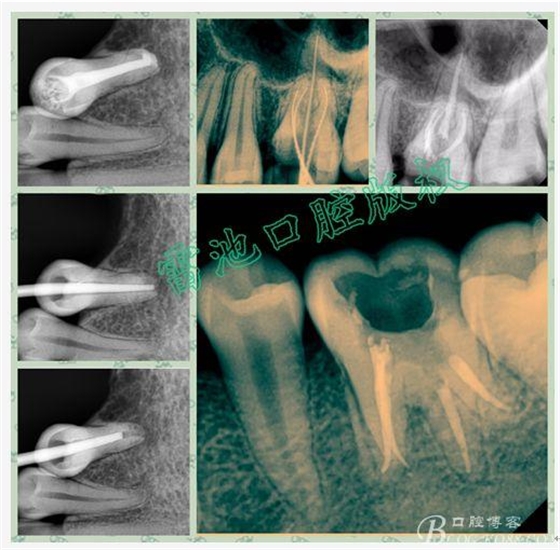

E、X線影像學(xué)的檢查研判能力:這點(diǎn)不需要強(qiáng)調(diào)太多,對(duì)于普通的非CBCT的二維影像對(duì)醫(yī)生讀片能力有一定的要求,有個(gè)逐步提高的過(guò)程,非一蹴而就,需要學(xué)會(huì)把二維的X線影像與三維的解剖結(jié)構(gòu)進(jìn)行良好的對(duì)應(yīng)結(jié)合,對(duì)于某些鈣化的髓室底,應(yīng)通過(guò)想象把根管口的分布、根管的走向以及各種變化通過(guò)想象投射到對(duì)應(yīng)的髓室底上;

常規(guī)后牙合面無(wú)齲壞的從髓角最高或者根管最粗大的對(duì)應(yīng)合面點(diǎn)開(kāi)髓,對(duì)于牙位不正,髓室影像不清時(shí),開(kāi)髓方向直接朝向最大的根管一般是沒(méi)有錯(cuò)的,個(gè)別特殊情況下,可能需要從其它牙面開(kāi)髓,而不是舌側(cè)或者合面,比如扭轉(zhuǎn)擁擠的下切牙或者尖牙,某些時(shí)候需要從唇面開(kāi)髓,還有一種對(duì)有全冠修復(fù)的牙在不拆除冠修復(fù)情況下開(kāi)髓可能面臨的問(wèn)題要有認(rèn)真的思考,因?yàn)槿谛迯?fù)體掩蓋了原始的真實(shí)牙體及牙根結(jié)構(gòu),冠的舌側(cè)和合面形態(tài)不能作為開(kāi)髓的解剖標(biāo)志;前牙注意防止通路偏斜,包括近遠(yuǎn)中或者唇舌側(cè)偏斜,尤其對(duì)于過(guò)度外翻或者內(nèi)傾,以及扭轉(zhuǎn)牙,腦中要有牙體全局觀,做到“胸中有牙,手上不抖”,如果找不到落空感或者探查無(wú)根管口,不要盲目下鉆,自我想當(dāng)然以為髓腔鈣化,這時(shí)候冷靜分析,及時(shí)插針進(jìn)行影像學(xué)檢查是明智的選擇,時(shí)刻記住“不作死就不會(huì)死”的格言,而對(duì)于后牙有齲壞,建議從齲壞位置開(kāi)始下鉆再根據(jù)常規(guī)根管分布情況合理設(shè)計(jì)開(kāi)髓外形,開(kāi)髓過(guò)程是一個(gè)動(dòng)態(tài)的過(guò)程,國(guó)外書(shū)上有一句關(guān)于開(kāi)髓的格言------開(kāi)髓就是 “尋找髓角”的過(guò)程,個(gè)人認(rèn)為這句話是非常有道理的,因?yàn)樗杞堑墓串?huà)有助于髓腔的初期空間定位,而開(kāi)髓不全是造成后牙根管定位困難的常見(jiàn)原因;

C、“牙本質(zhì)地圖”的識(shí)別:根管口的位置常??梢愿鶕?jù)髓室底牙本質(zhì)的牙色來(lái)推測(cè),這種方法被稱為“牙本質(zhì)地圖”,在微黃或者暗灰的牙本質(zhì)中發(fā)現(xiàn)白點(diǎn)、出血的紅點(diǎn)、或者失活劑處理的黑點(diǎn)都有可能就是根管口所在的位置,再結(jié)合牙體解剖結(jié)構(gòu)的分析對(duì)照與研判,通過(guò)8-10號(hào)擴(kuò)大針或者DG-16探針進(jìn)行探查證實(shí),特別提醒在根管未完全確認(rèn)之前不要急于把擴(kuò)大針或者其它根管銼插入過(guò)深,必要時(shí)結(jié)合X片影像學(xué)確認(rèn);